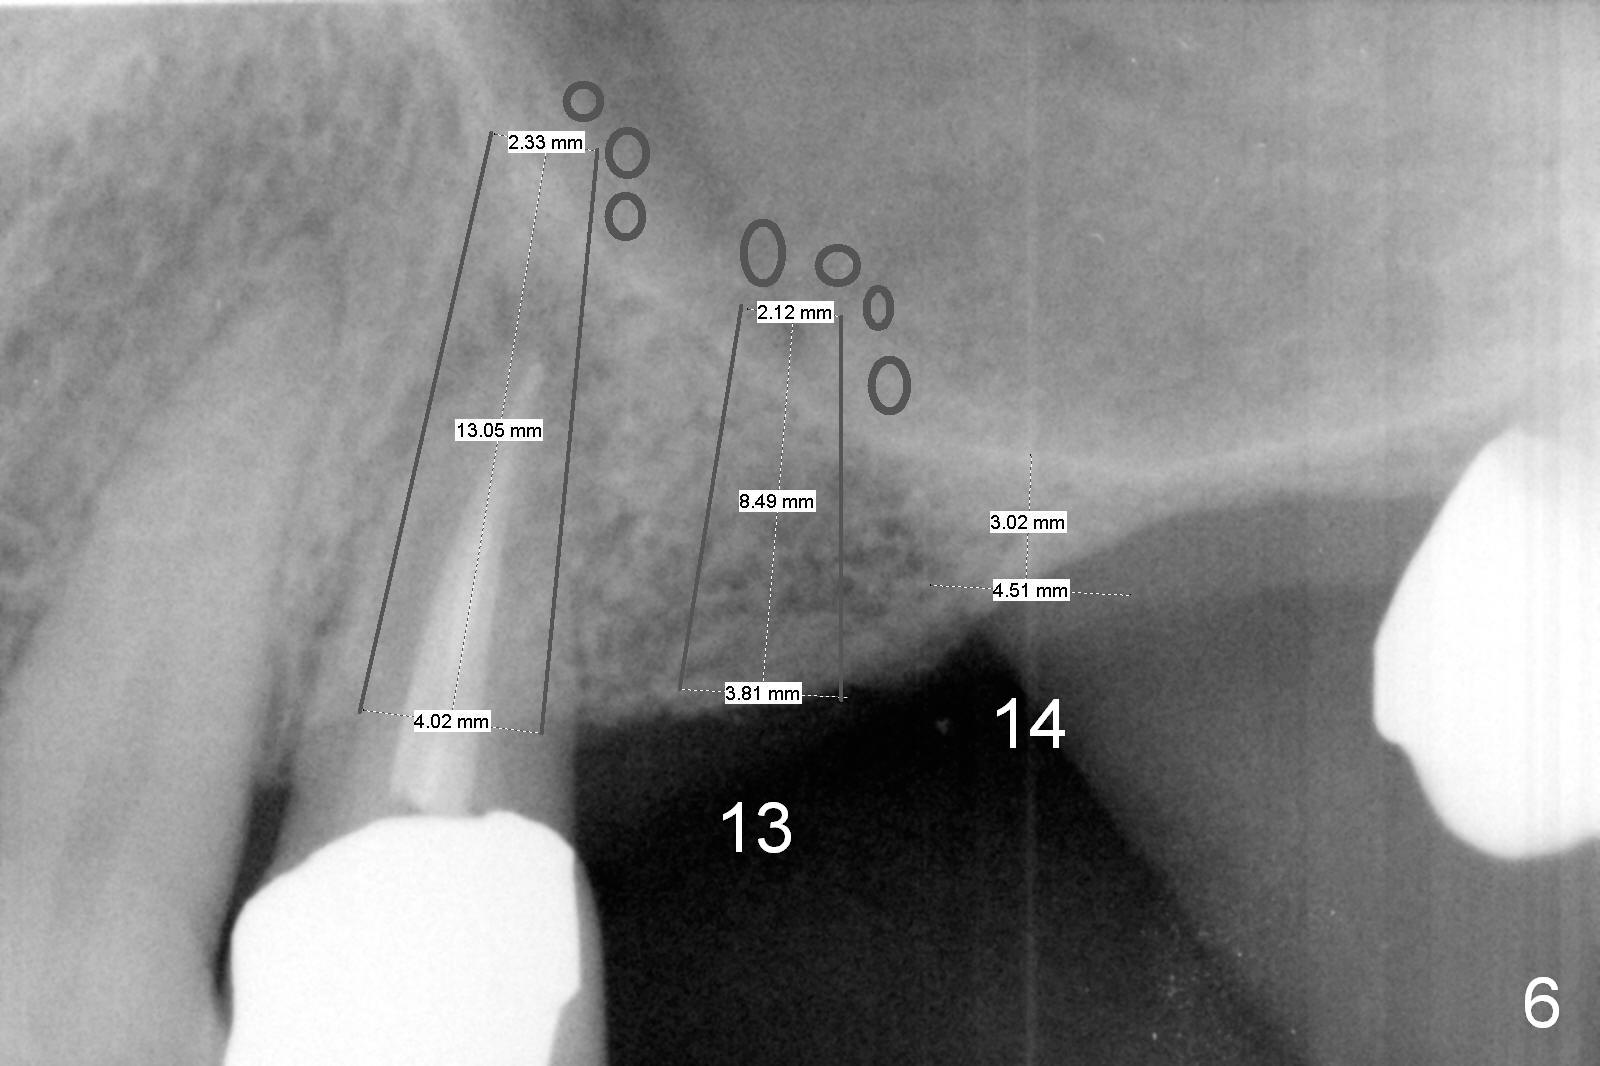

A 64-year-old man (MM) had caries at the tooth #12 (Fig.1), requiring root canal therapy (RCT, Fig.2). One year later, the periapical radiolucency reduces (Fig.3 <, as compared to that in Fig.2). The tooth remains asymptomatic 7 years posts RCT (Fig.4). A year later, the tooth has pain and buccal gingival swelling (probing tenderness); periradicular radiolucency is evident (Fig.5 arrowheads). It appears that the root fractures. Between the 7th and 8th years post RCT, the patient masticated mainly on the left side, while implants were placed at #30 and 31. The patient plans to have 4 implants in the upper left sextant (Fig.6). While implants are being placed at the site of #12 (Clindamycin) and 13, sinus lift seems mandatory at the sites of #13 and (initial depth will be 5-6 mm). By the time implants to be placed at #14 and #15, the bone height may increase.